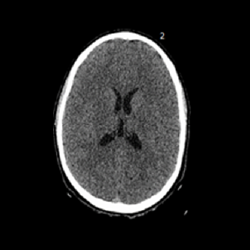

Por favor, inscríbete en curso antes de realizar este cuestionario. 1. Una de las maneras para diferenciar una asimetría ventricular y una hidrocefalia es mirar ¿qué astas?1 Temporales Occipitales Frontales 2. ¿A qué corresponde esta imagen?1 Megascisterna magna Higroma Espacio subracnoideo Quiste aracnoideo 3. La plagiocefalia postural se puede confundir con una craneosinostosis por sutura temprana de1 Coronal Lamboidea Metópica 4. ¿Qué variante anatómica vemos en la imagen?1 Quiste aracnoideo Cavum pellucidum Cavum interpositum Cavum vergae ¿Cómo interpretar una tomografía? Módulo 2 - Anatomía Volver a: Errores radiológicos